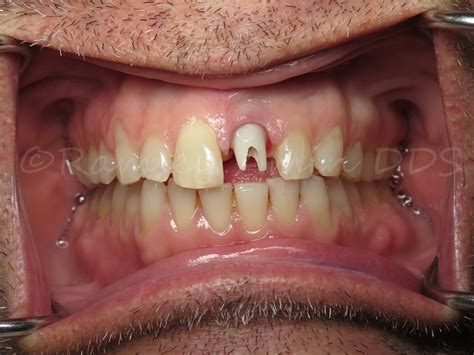

Implant Placement Surgical insertion of the titanium post into the jawbone.

Osseointegration A healing period of 3–6 months where the bone fuses to the implant.

The success of an implant in the front of the mouth often depends on the quality of the surrounding gum tissue. Surgeons pay special attention to the "emergence profile," which is how the crown emerges from the gum line, ensuring it looks identical to a natural tooth rather than a prosthetic attachment.